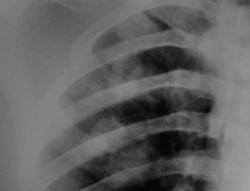

Парень, 17 лет. Поступил в тяжелом состоянии, без сознания. Впервые недомогание почувствовал в сентябре, лечился в районе. До этого был здоров, закончил кадетское училище, поступил в училище летчиков гражданской авиации. На УЗИ лимфоаденопатия, кисты в печени. Периферических лимофоузлов нет. В настоящее время госпитализирован в гематологию с предварительным диагнозом лимфома Беркитта.

Какой интересный и показательный случай. На рентгенограмме множественные метастазы. Соглашусь с Татьяной Валентиновной, недовно наблюдал такие - первичный очаг - семинома.

Я точно также думаю, что это метастазы, предположила яичко, почку, а также меланому. Больной очень тяжелый, без сознания. Мы даже КТ с услением не стали делать. Не знаю жив ли он еще. А в гематологию его положили, потому, что в другие отделения с метастазами его не могли положить. Перевезти его в онкодиспансер или отправить его домой в район тоже не решились, он мог не доехать. Вот и получилась лимфома. В головном мозге по плотности похоже на метастазы меланомы, но первичного очага нет. Лимфомы (злокачетсвенны) могут метастазировать в головной мозг, но они менее плотные

К сожалению об УЗИ я узнала после того как больного увезли в отделение, иначе бы сразу же сделала бы брюшную полость. Легкие также сняли позже. Потом оказалось, что легкие ему снимали в районе, видели там метастазы, но снимки не привезли. Вот так вот, больной экстренный из приемного отделения, давай-давай, давай быстрей, а нейрохирургов интересовал только головной мозг.